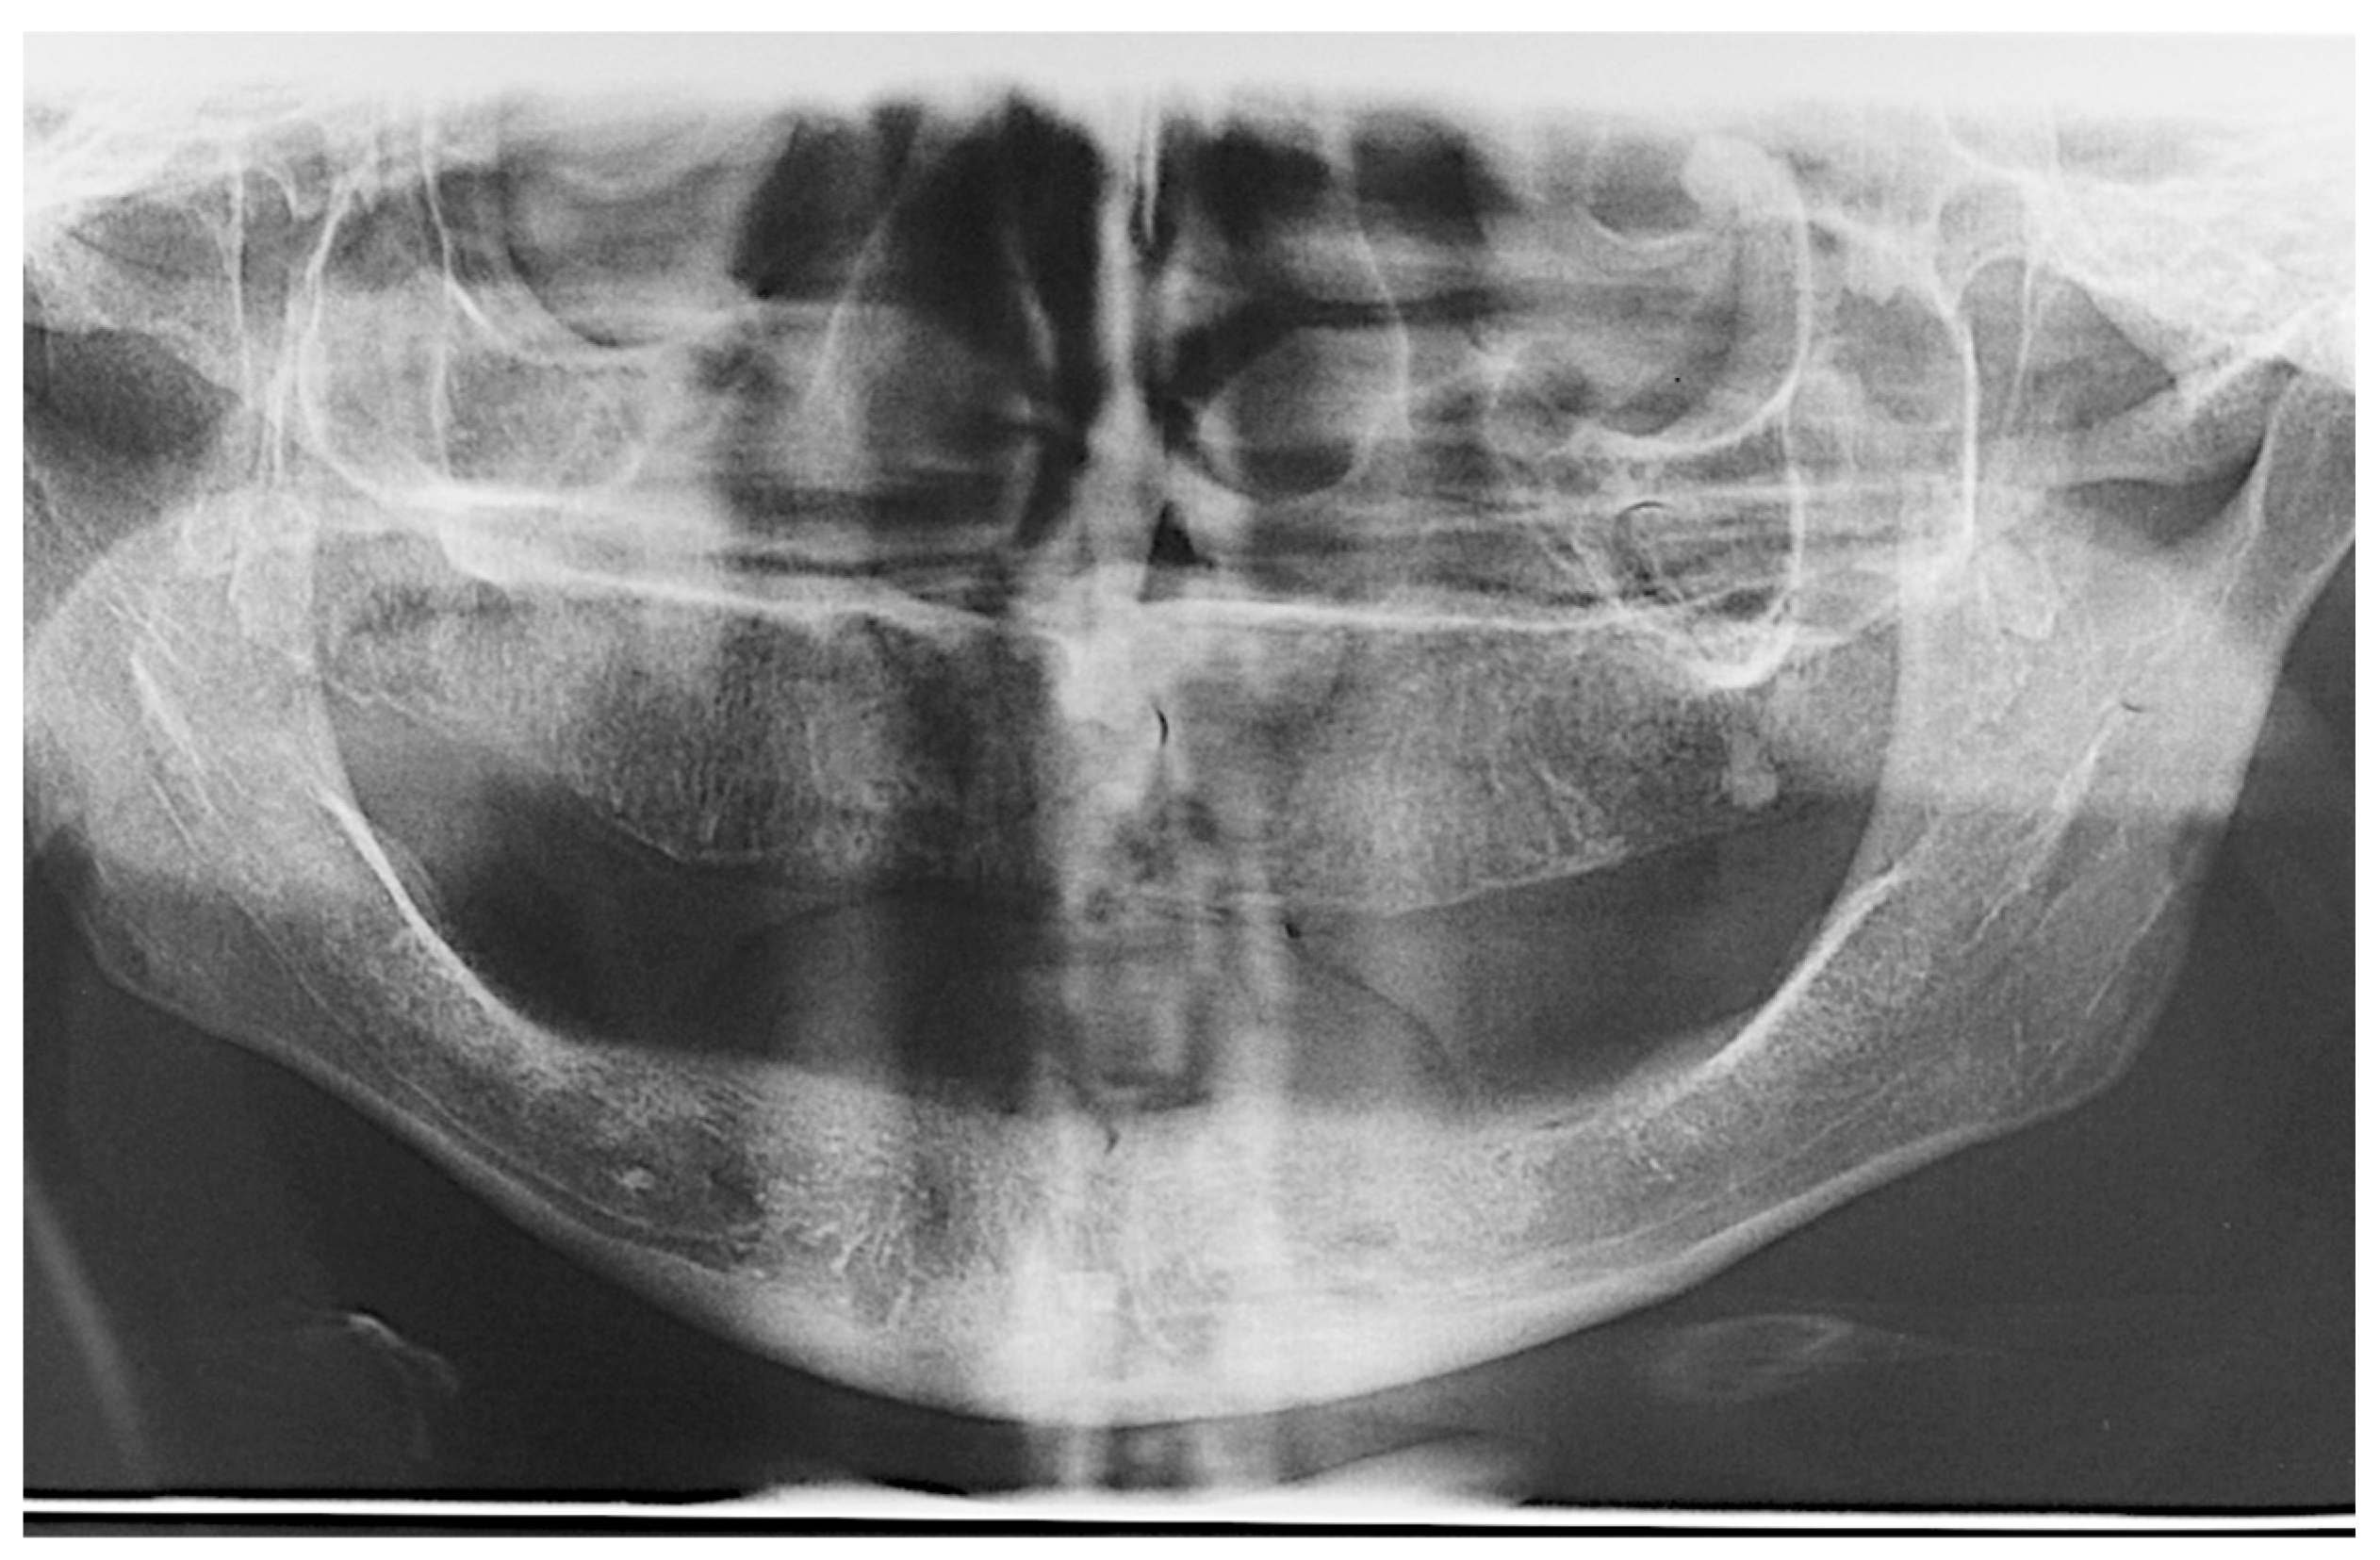

The patients were offered all possible treatment options, so they could choose which treatment plan was more adequate for each patient. Those enrolled in the study chose the procedure and authorized it by signing a term of consent in accordance with the Helsinki Declaration (1975, revised in 2013). The primary goal was to achieve sufficient initial stability to perform immediate loading, and thus, in some cases, sub-instrumentation of the implant sites could be performed in order to ensure this objective. The choice for sub-instrumentation was left for the surgeon to decide, regardless of the region, whenever they felt the bone density appeared to be D3 or D4 [18], according to their experience. In regions with a denser bone or cortical (D1 or D2), conventional instrumentation was performed. At least 45 Ncm of initial torque was necessary to continue with the immediate loading, but higher values could be reached if possible [12]. Diagnosis and treatment planning included study models articulated in a semi-adjustable articulator, clinical photographs, panoramic radiographs (Figure 1) and cone-beam computed tomography (CBCT) imaging exams to identify the anatomical structures and visualize the presence of any pathology. After the oral rehabilitation project was ready, a multifunctional guide to determine the best implant placement positions was fabricated.

Figure 1.

Baseline panoramic radiograph.